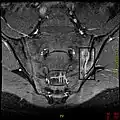

T1-weighted MRI with fat suppression after administration of gadolinium contrast showing sacroiliitis in a person with ankylosing spondylitis

If these criteria still do not give a compelling diagnosis magnetic resonance imaging (MRI) may be useful.[21][23] MRI can show inflammation of the sacroiliac joint.

Options for earlier diagnosis are tomography and MRI of the sacroiliac joints, but the reliability of these tests is still unclear.